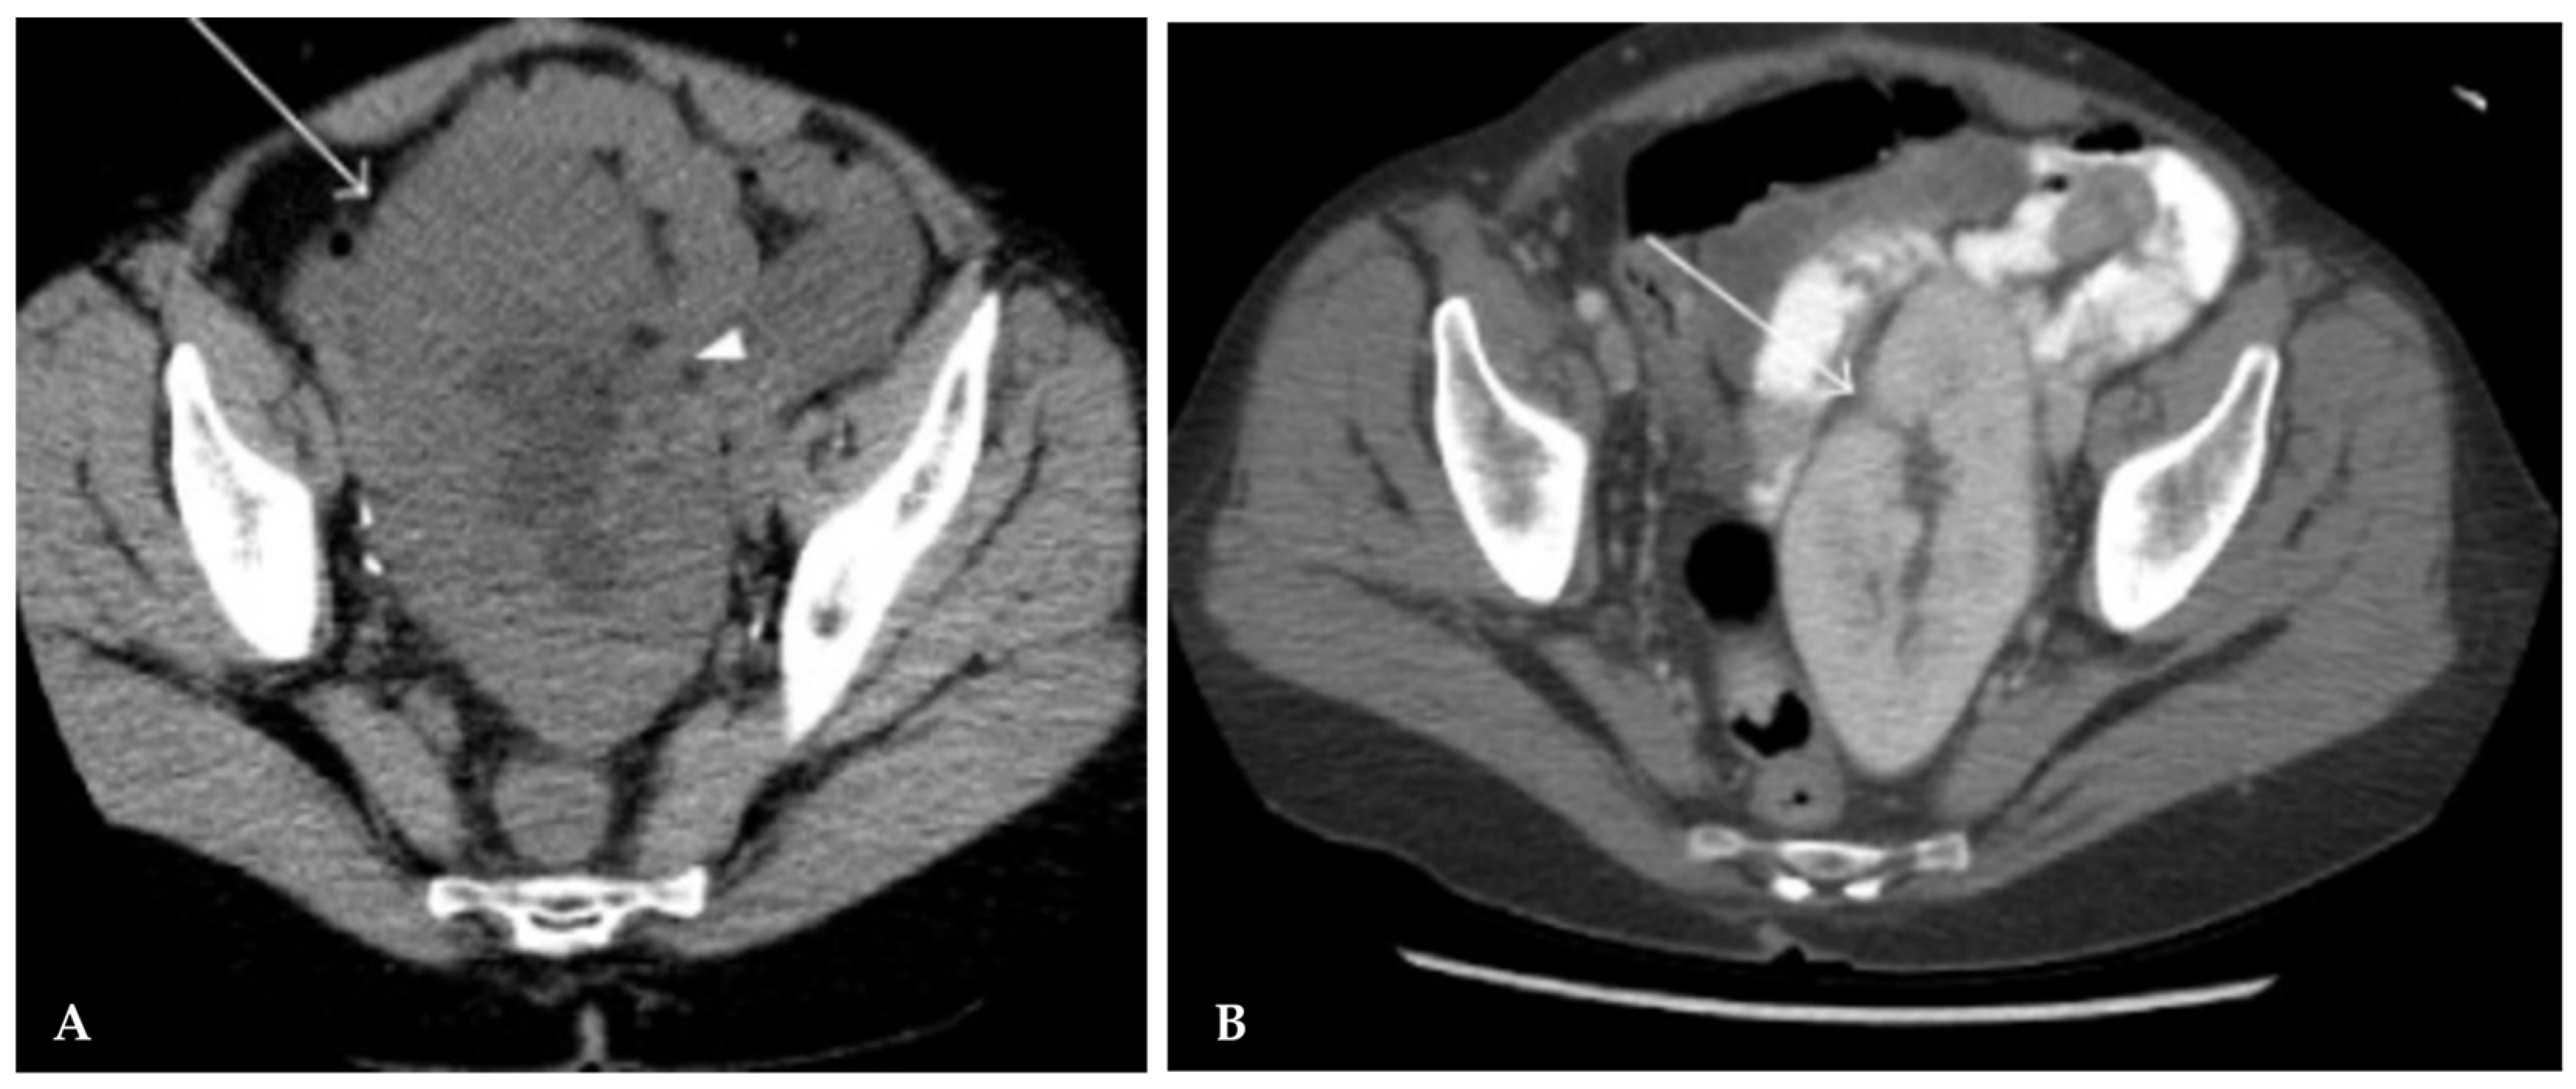

3.2. Vascular Thrombosis

3.2.1. Venous Thrombosis

- Cambou, L.; Millet, C.; Terrier, N.; Malvezzi, P.; Timsit, M.-O.; Anglicheau, D.; Badet, L.; Morelon, E.; Prudhomme, T.; Kamar, N.; et al. Management and Outcome After Early Renal Transplant Vein Thrombosis: A French Multicentre Observational Study of Real-Life Practice Over 24 Years. Transpl. Int. 2023, 36, 10556. [Google Scholar] [CrossRef]

- Santos, J.E.; Gaspar, A.; Querido, S.; Jorge, C.; Weigert, A.; Gabriel, H.M.; Martinho, A.; Machado, D. Unexpected success in early post-transplantation renal vein thrombosis: A case report and literature review. Clin. Nephrol. Case Stud. 2021, 9, 19–25. [Google Scholar] [CrossRef]